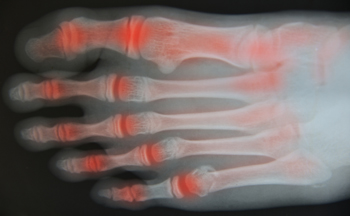

Arthritic Foot Care

Arthritis is a joint disorder that involves the inflammation of different joints in your body, such as those in your feet. Arthritis is often caused by a degenerative joint disease and causes mild to severe pain in all affected areas. In addition to this, swelling and stiffness in the affected joints can also be a common symptom of arthritis.

Alleviating Arthritic Pain

- Exercises that stretch the foot can prevent further pain and injury and increase mobility

- Most of the pain can be alleviated with anti-inflammatory drugs, heat, and topical medications

- Massages can help temporarily alleviate pain.